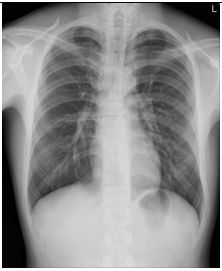

4. 39 y/o female, productive cough for 2 months